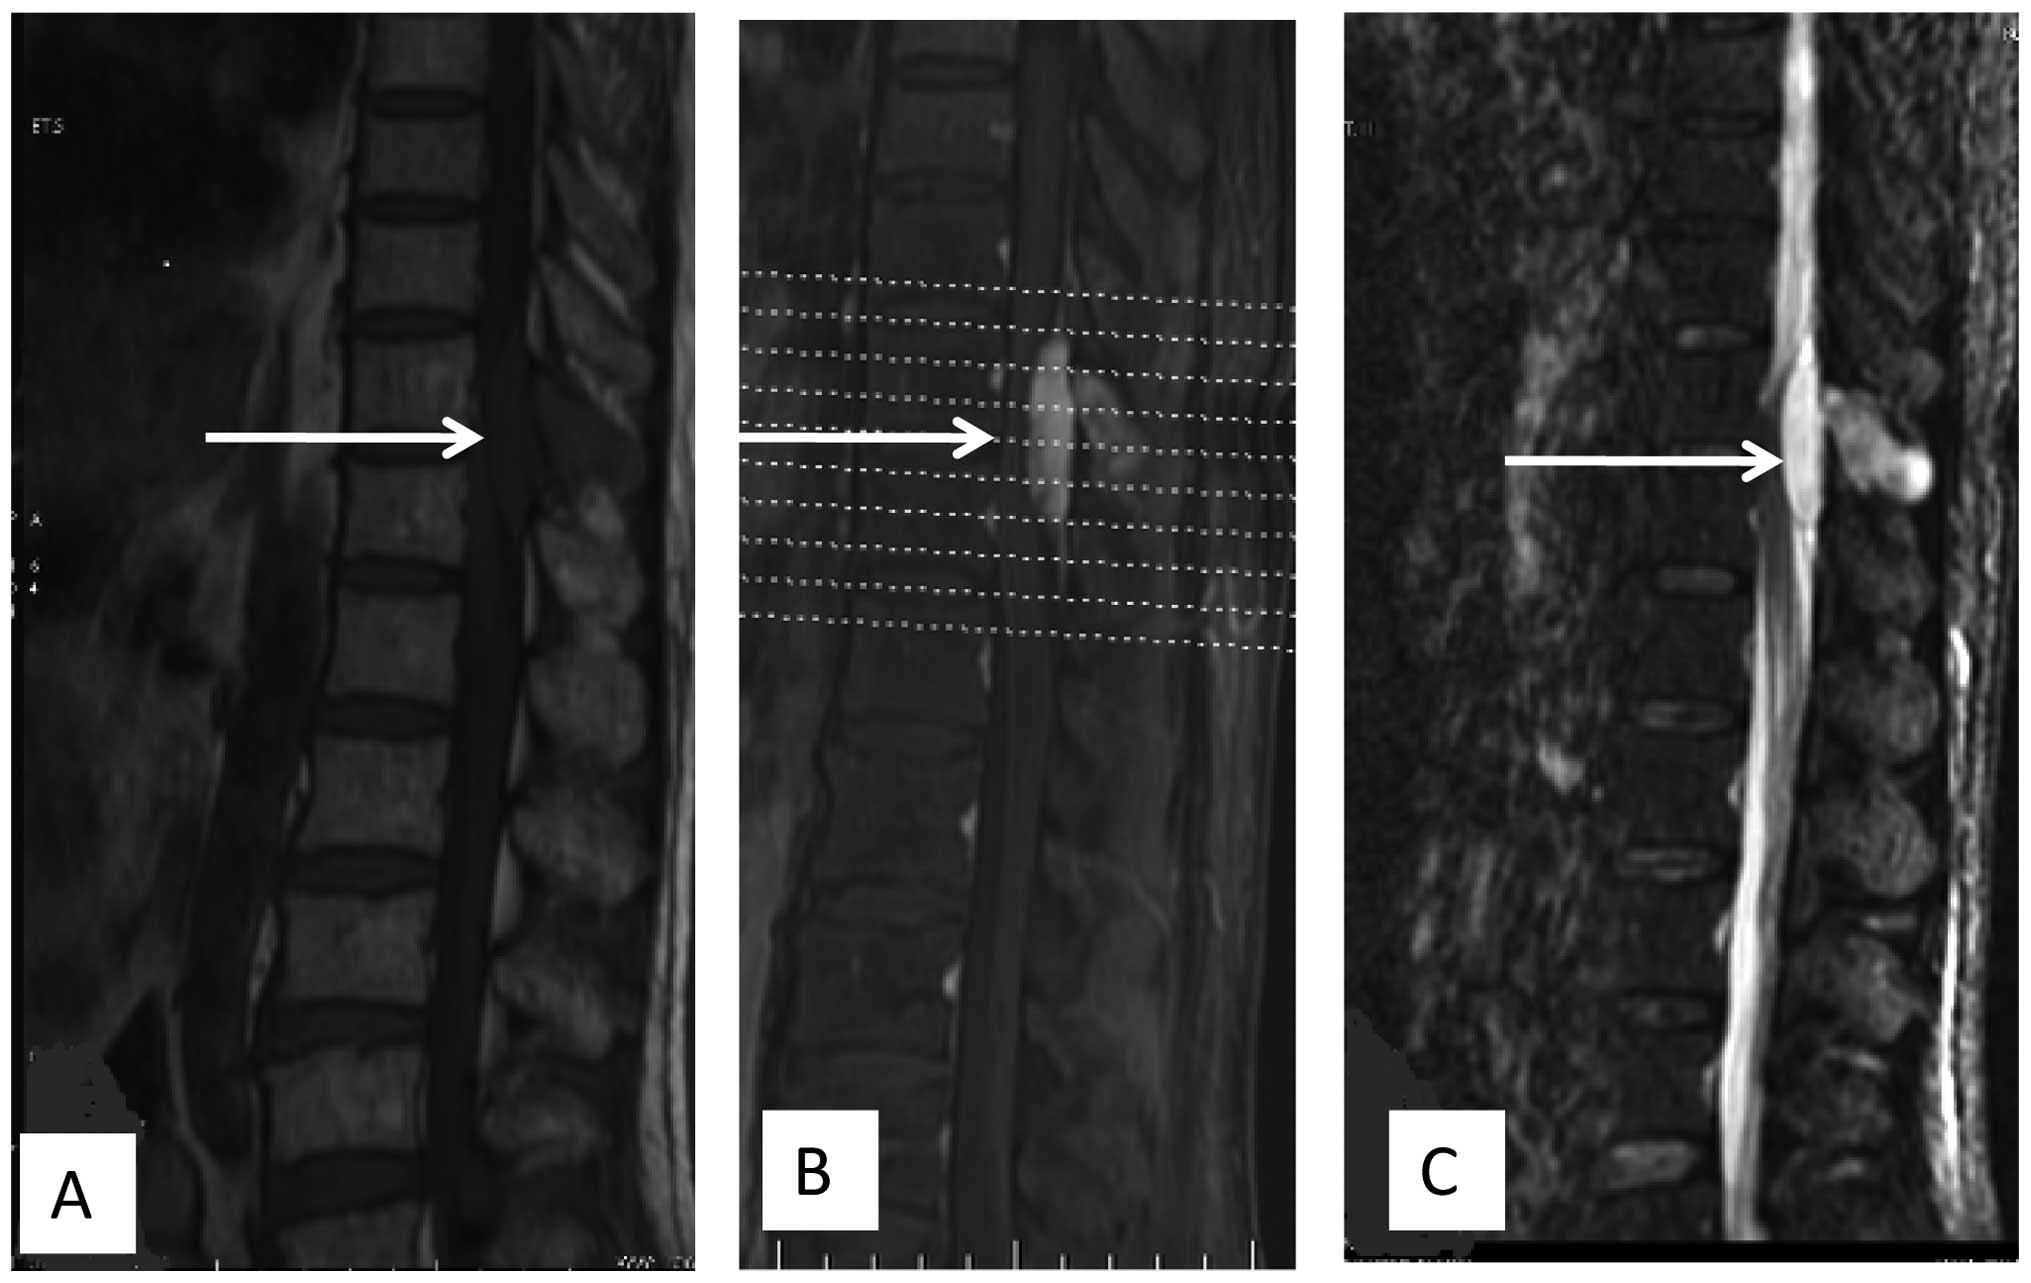

Following recovery from the surgery, radiotherapy was administered at 48 Gy for 24 fractions over 5 weeks. At 1 week after the initiation of radiotherapy, concurrent chemotherapy consisting of gemcitabine (0.8 g/m2 on days 1 and 8) and docetaxel (75 mg/m2 on day 8) was administered. The adverse events were mild, such as leukopenia of World Health Organization grade I (4). At 16 days post-radiotherapy, a second course of chemotherapy with the same regimen was administered. Another 18 days later, computed tomography (CT) detected a 4.5×3.7-cm mass in the abdominal cavity below the gastric body. Several days later, the patient started complaining of blurred vision and painless diplopia in the left eye. Proptosis of the left eye became progressively evident. MRI showed a retrobulbar mass, which was isointense on T1-weighted images and hypo- to isointense on T2-weighted images, with ring enhancement following gadolinium-DTPA infusion (Fig. 2). The mass slightly compressed the optic nerve. The diagnosis was of an orbital metastasis. To alleviate the eye symptoms, the patient received palliative radiotherapy (21 fractions of 51 Gy over 10 weeks) to the retrobulbar mass. During the radiotherapy, the patient developed multiple metastases in regions that included the pelvic cavity, the pelvis femur and the lumbar vertebrae, and progression of the orbital mass was observed (Fig. 3). However, there was no involvement of the lungs. Although the patient received second-line chemotherapy with ifosfamide (1.8 g/m2 on days 1 to 5) and epirubicin (60 mg/m2 on days 1 and 2), the disease progressed and the patient's performance state deteriorated. The patient succumbed to the disease 3 months later.

Figure 2.

Axial magnetic resonance imaging showing a retrobulbar mass lesion producing (A) isointense signals on T1-weighted imaging and (B) hypo- to isointense signals on T2-weighted imaging, with (C) ring enhancement in the left eye. The mass slightly compressed the optic nerve.